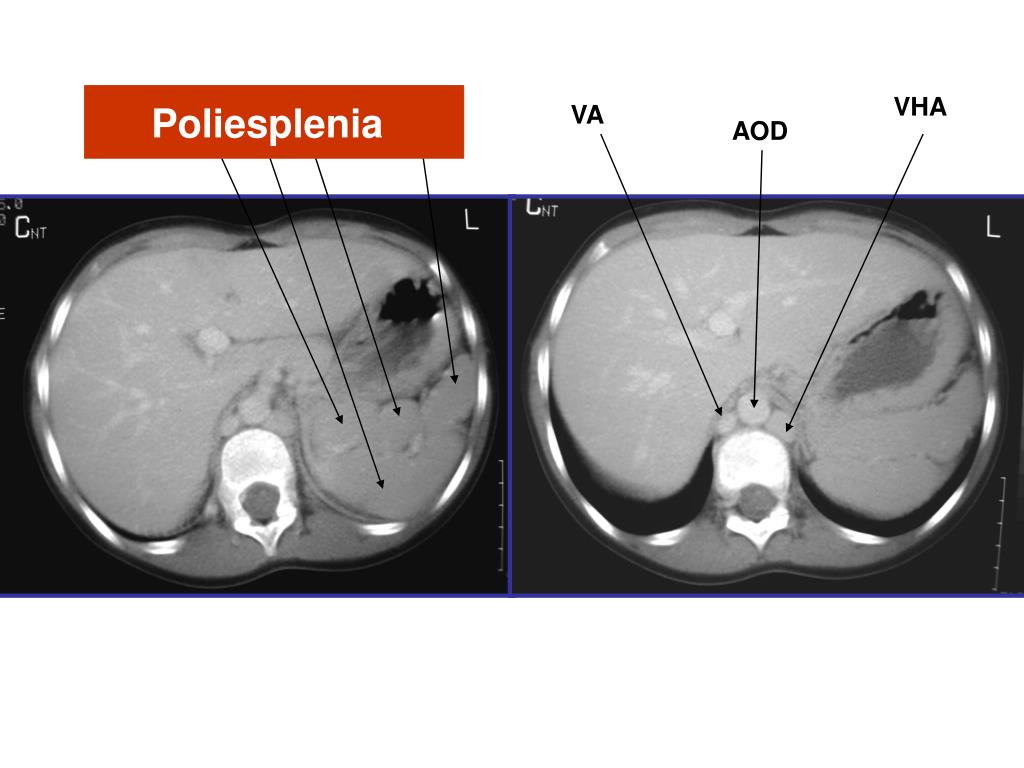

41. VHA Poliesplenia VA AOD

4. AA = aorta ascendente AD = aurícula derecha AI = aurícula izquierda AOD = aorta descendente APD = arteria pulmonar derecha API = arteria pulmonar izquierda ASD = arteria subclavia derecha ASI = arteria subclavia izquierda CIA = comunicación interauricular CIV = comunicación interventricular VCSD= vena cava superior derecha COA = coartación de aorta DUC = ductus arterioso EP = estenosis pulmonar GLENN operación de = conexión VCSD-APD SC = seno coronario TP = tronco pulmonar TF = tetralogía de Fallot TGV = transposición de grandes vasos VA = vena ácigos VCID = vena cava inferior derecha VCII = vena cava inferior izquierda VCSD = vena cava superior derecha VCSI = vena cava superior izquierda VD = ventrículo derecho VHA = vena hemiácigos VI = vena innominada VI = ventrículo izquierdo VPD = vena pulmonar derecha VPI = vena pulmonar izquierda VSD = vena subclavia derechA VSH = venas suprahepáticas VSI = vena subclavia izquierda ABREVIATURAS DE TRAYECTOS